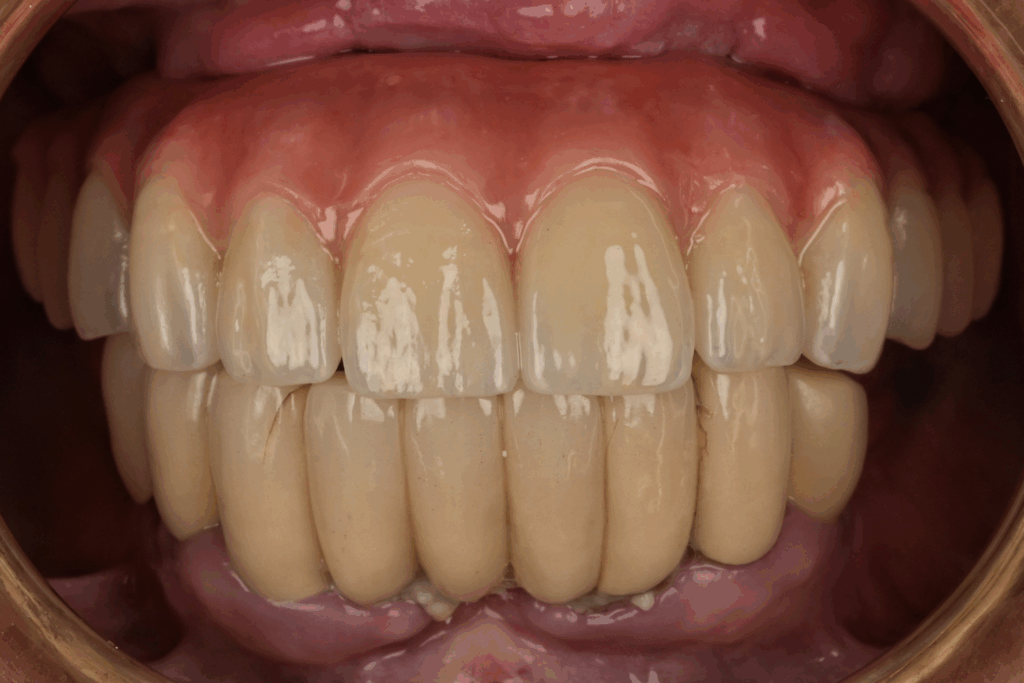

案例4. 上顎All on X

Before

After